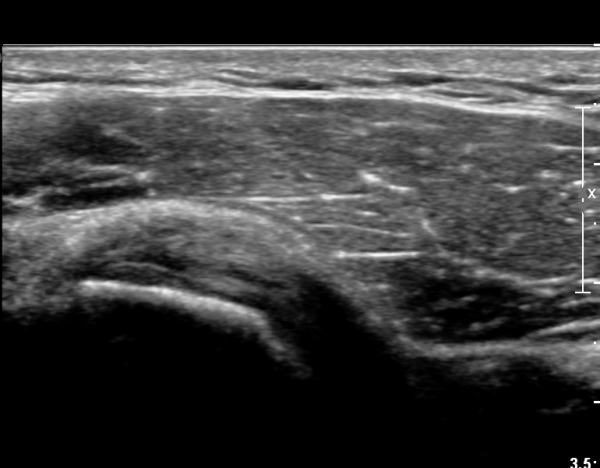

ŽÃËÀÚ¸¦ À§. ¾Æ·¡ ¹æÇâÀ¸·Î µ¹·Á °ß°©ÇϱٰÇÀÇ È¾´Ü¸é°Ë»ç¿¡¼­µµ °ß°©ÇϱٰÇÀÇ

°Ç ½ÇÁú³» ÆÄ¿­ÀÌ °üÂûµÈ´Ù(»çÁø 4, 5).